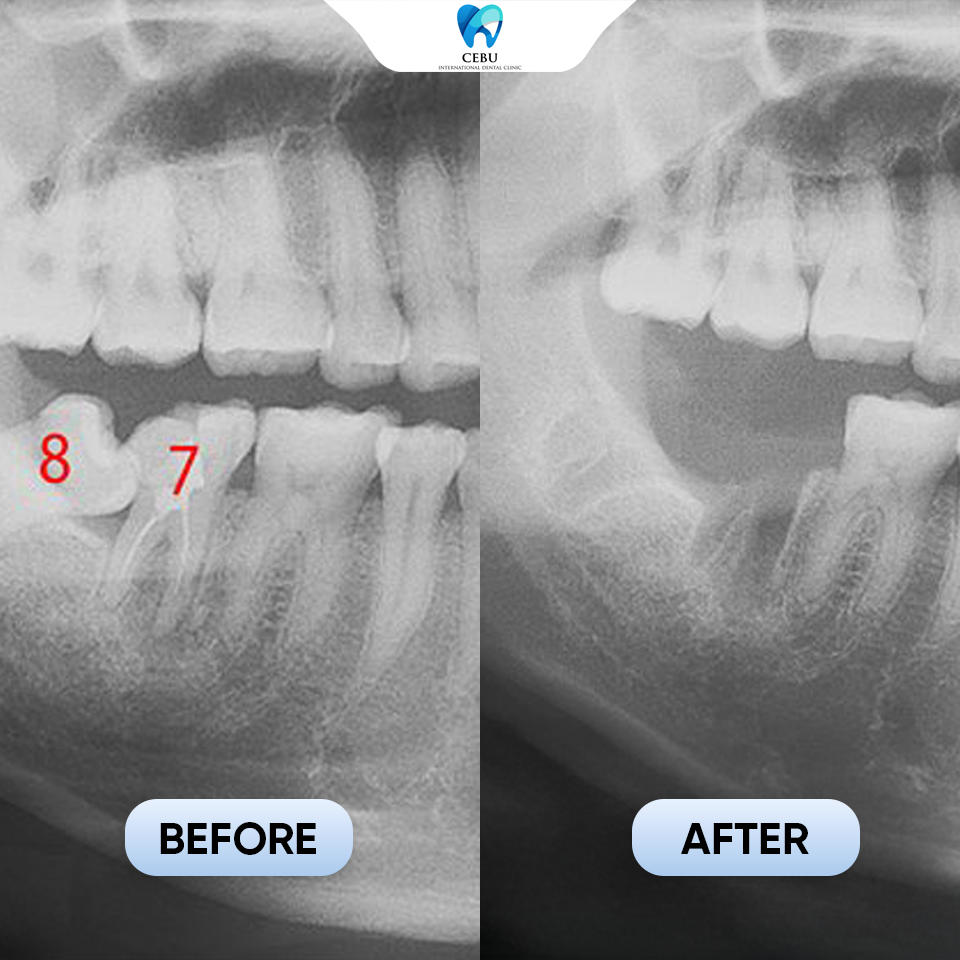

Serious dental risks you face when leaving wisdom teeth untreated today A Wisdom Tooth may seem harmless at first, but improperly erupted wisdom teeth can ...

Serious dental risks you face when leaving wisdom teeth untreated today A Wisdom Tooth may seem harmless at first, but improperly erupted wisdom teeth can lead ...